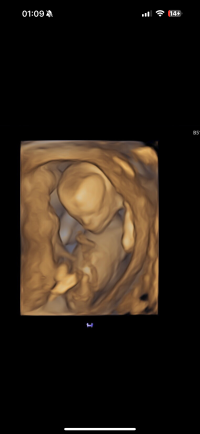

Vil du se om skull theory er mulig på mine bilder??Synes ikke nuben synes så godt? Litt gutt ifølge skull theory

Gjetter jente for moroskyldVil du se om skull theory er mulig på mine bilder??

Vanskelig å siDu kan alltids spørre ChatGPT, det gjorde jeg, men tar det med en klype saltVil du se om skull theory er mulig på mine bilder??

Veldig, har sett i grupper at den tar feil stort sett hver gangDu kan alltids spørre ChatGPT, det gjorde jeg, men tar det med en klype salt![]()

Absolutt, spurte den om hvilken kjønn den så på ultralyden i følge Nub teorien, vel vitende at bilde ikke viste underkroppen, den ringet ut noe helt random og sa et kjønn utifra det, trodde den var glupereVeldig, har sett i grupper at den tar feil stort sett hver gang![]()